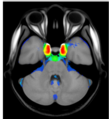

A statistical atlas of cerebral arteries

Magnetic resonance angiography (MRA) can capture the variation of cerebral arteries with high spatial resolution. These measurements include valuable information about the morphology, geometry, and density of brain arteries, which may be useful to identify risk factors for cerebrovascular and neurological diseases at an early time point. However, this requires knowledge about the distribution and morphology of vessels in healthy subjects. the statistical arterial brain atlas described in this work is a free and public neuroimaging resource that can be used to identify vascular morphological changes. The atlas was generated based on 544 freely available multi-center MRA and T1-weighted MRI datasets. the arteries were automatically segmented in each MRA dataset and used for vessel radius quantification. The binary segmentation and vessel size information were non-linearly registered to the MNI brain atlas using the T1-weighted MRI datasets to construct atlases of artery occurrence probability, mean artery radius, and artery radius standard deviation. This public neuroimaging resource improves the understanding of the distribution and size of arteries in the healthy human brain.

The statistical atlas consists of four image files in the niftii format and in MNI reference space (0.5 mm^3). These files include the TOF MRA average atlas (tofAverage.nii.gz), the vessel probability atlas (vesselProbabilities.nii.gz [in %]), the mean artery radius atlas (vesselRadius.nii.gz [in mm]), and the standard deviation of the artery radius atlas (vesselRadiusStd.nii.gz [in mm]). All images are saved using float values. The TOF MRA and T1-weighted datasets used for atlas generation can be downloaded from the original sources.

Time of flight atlas Probabilistic vessel atlas Radius vessel atlas (average) Radius vessel atlas (standard deviation)Publication: